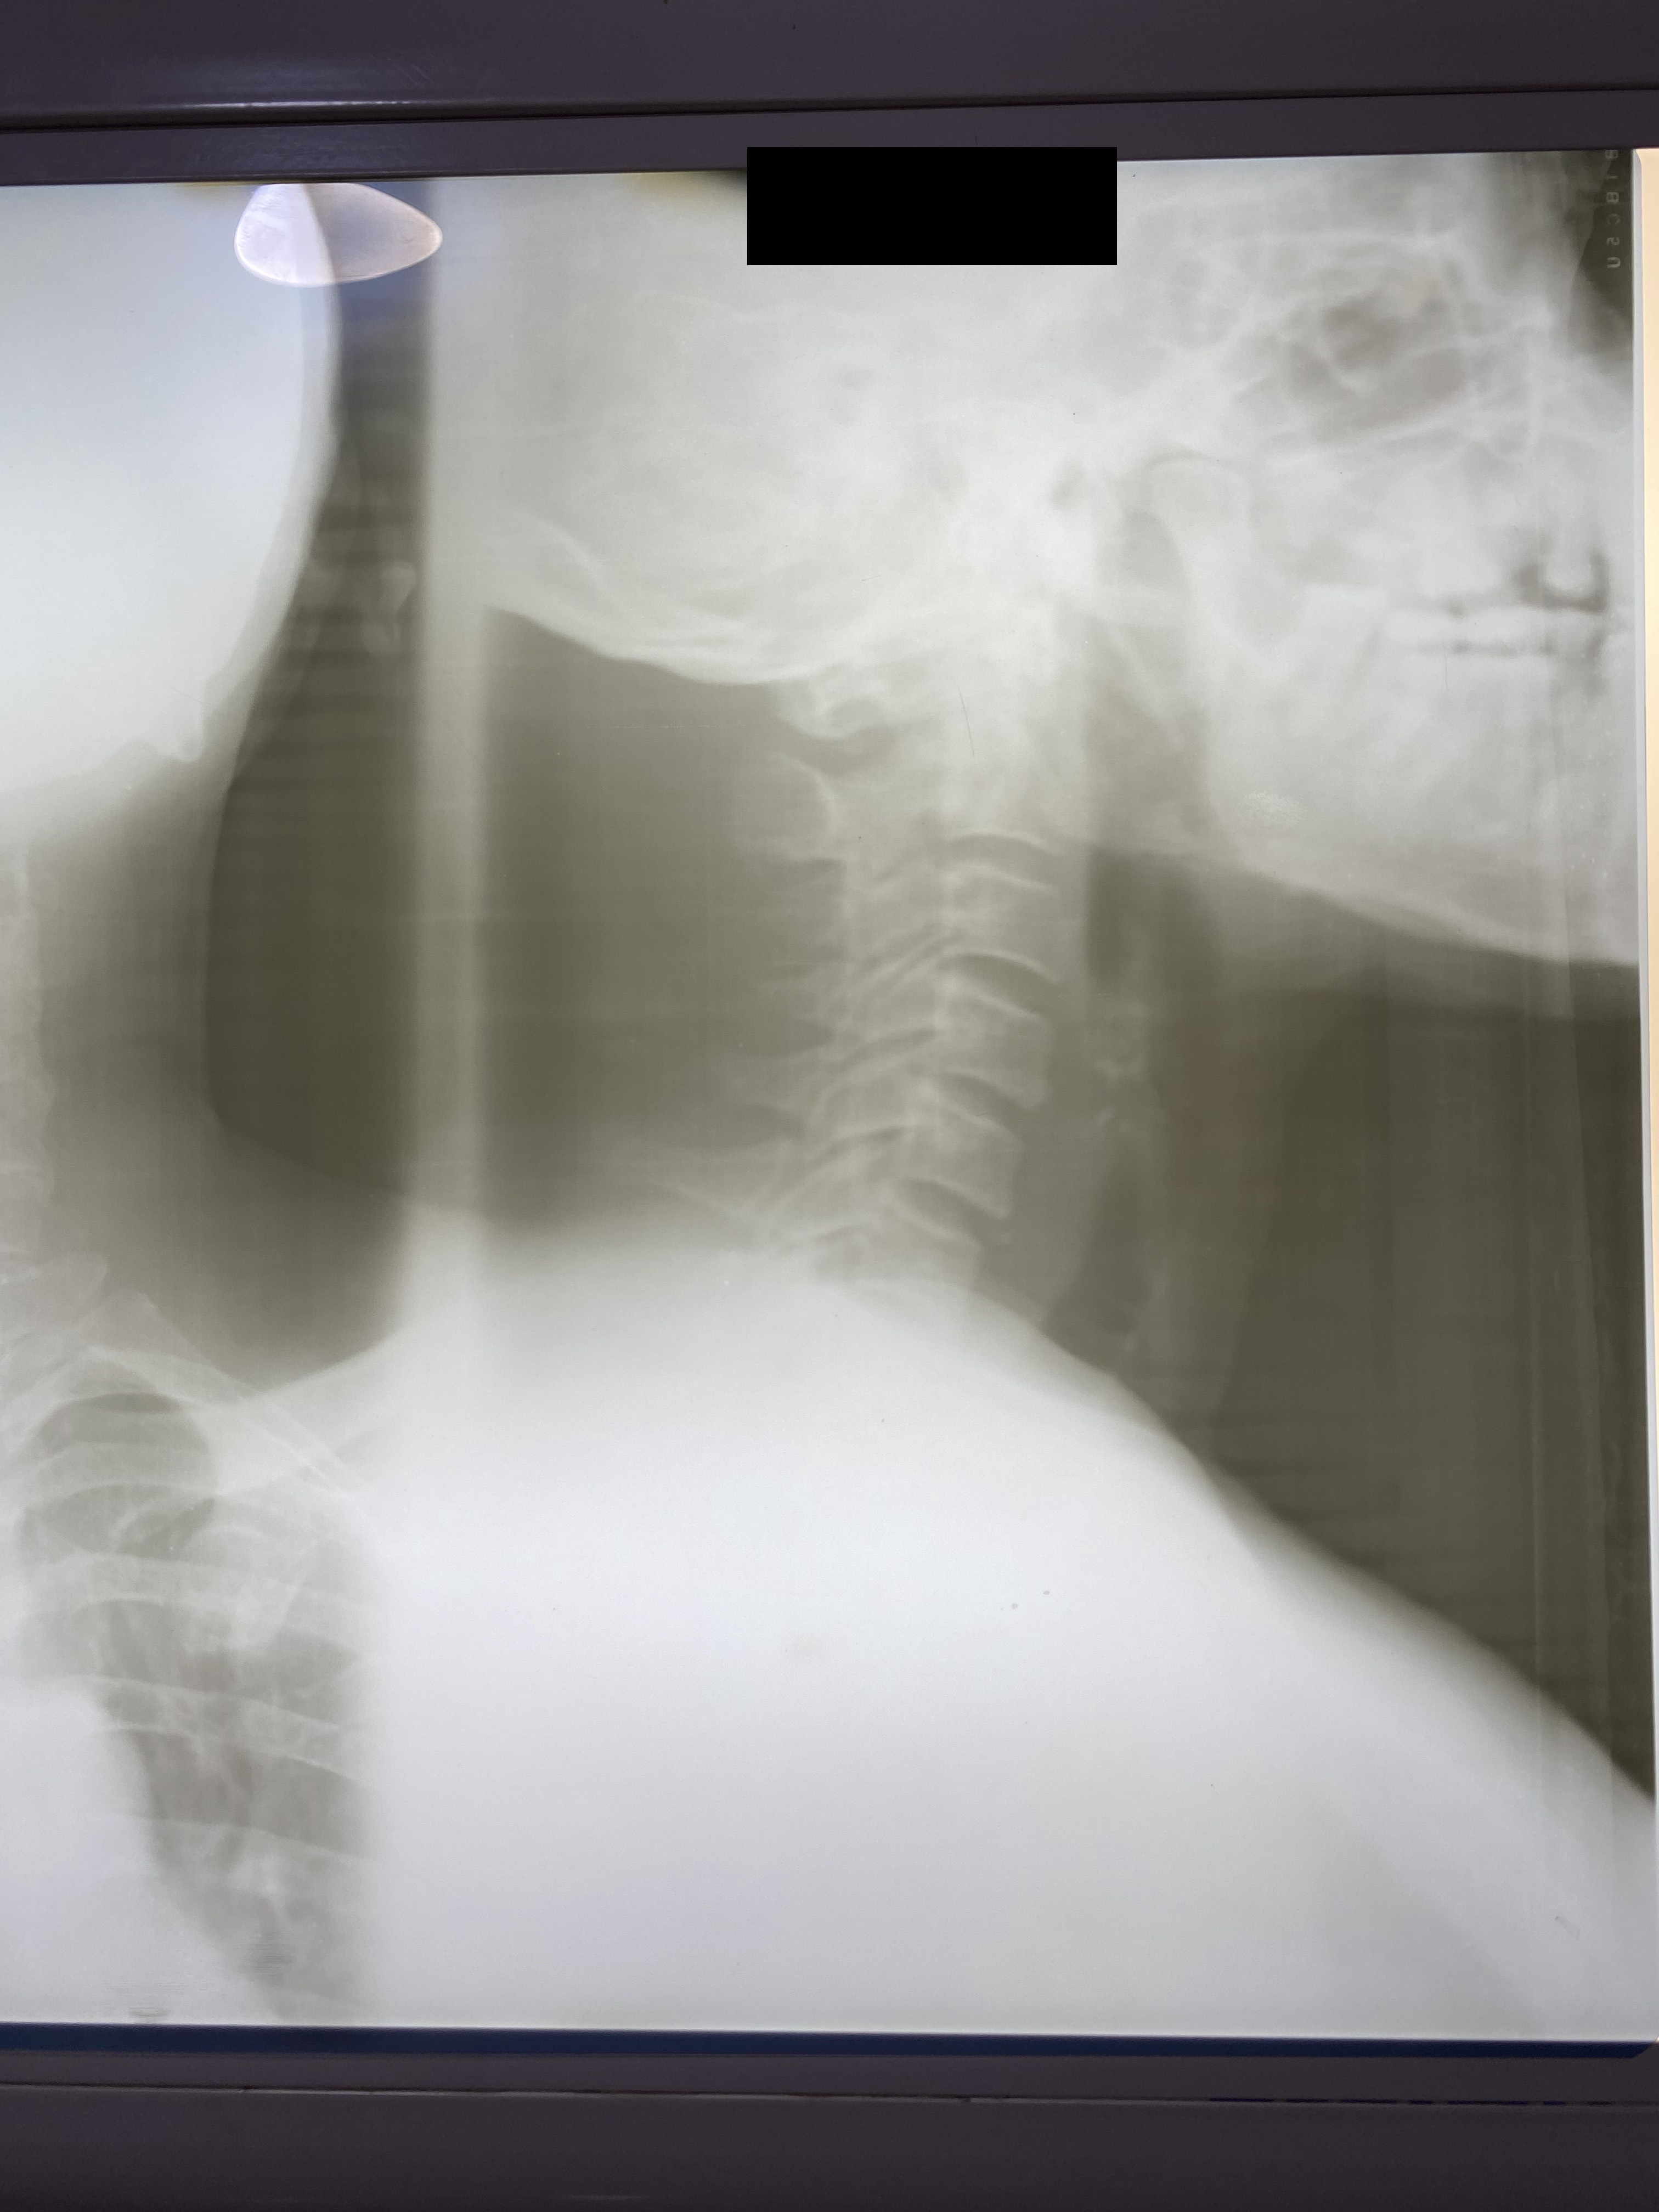

Chiropractic X-Rays

In partnership with Nova Wellness Centre led by Dr Asheley Ashietey in Accra, we conducted chiropractic examinations of 100 women working as kayayei in Kantamanto Market ranging in ages from 15 to 44, with varied experience carrying in the market from those who had been working for a few weeks to some women who had carried bales for 20 years. Nearly every study participant reported significant pain as a result of headcarrying and x-rays indicated spinal deterioration and deformities beginning within months on the job. Such physiological impacts coupled with severely polluted, cramped and violent living conditions set the stage for catastrophic injury.